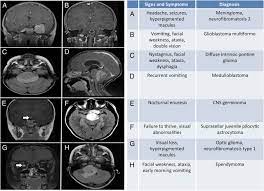

Signs Of Childhood Brain Tumors : Brushing Up On The Signs And Symptoms Of Childhood Brain T Flickr / Data were collected from the medical records of the patients (aged:. This can be caused by growth of the tumor, swelling in the brain, or blocked flow of cerebrospinal fluid. Symptoms may occur when a tumor presses on a nerve or damages certain parts of the brain. Symptoms from pediatric brain tumors vary widely, depending upon the tumor's location and size. This is a study of the presenting features of brain tumors in children, their localization and histology which is aimed at describing the most frequent symptoms at the beginning and at the moment of diagnosis and minimize the time needed to reach a diagnosis. Or, the cause of a symptom may be a different medical condition that is not a brain stem glioma.

Brain tumor signs and symptoms morning headache or headache that goes away after vomiting. Nausea and vomiting are two common signs of the flu or flulike illnesses. Signs or symptoms of brain tumors will depend on things such as the age of the child and the location of the tumor in the brain. Primary brain tumors start in the brain and usually do not spread outside the brain tissue. Symptoms may include headache, vomiting, nausea and personality changes.

Most commonly, children present with symptoms described below. This is the front of the brain. Many symptoms are related to an increase in pressure in or around the brain. Most brain tumors in children start in the lower parts of the brain, such as the cerebellum or brain stem. A brain tumor is an abnormal growth of tissue in the brain. However, in rare instances, these symptoms can be due to a brain tumor causing increased pressure inside the brain. Tumors at the base of the brain often cause headaches, vomiting, and behavioral changes because they block the normal passage of cerebrospinal fluids, causing the pressure within the head to rise. You can detect brain tumor in your child with the help of some signs and symptoms. This can be caused by growth of the tumor, swelling in the brain, or blocked flow of cerebrospinal fluid. These will depend on the size of the tumour, where it is and how it affects that part of the brain. If your child has a brain or spinal cord tumor, knowing what to expect can help you cope. General symptoms tumors in any part of the brain might raise the pressure inside the skull (known as intracranial pressure). The main parts of the brain are:

The most common forms of brain tumors are: The most common brain tumor in children is medulloblastoma. Check with your child's doctor if your child has any of the following: There are many other that affect children, including astrocytomas, gliomas, ependymomas, germinomas and more. Symptoms of brain tumors in children symptoms of brain tumors in children vary depending on the size, location, type and grade of the tumor.

Brain Tumour Foundation Of Canada It S Childhoodcancerawarenessmonth Please Share The Signs And Symptoms Of Pediatric Brain Tumours Earlier Diagnosis Could Lead To A Better Outcome Https Braintumour Ca 5176 Childhood Cancer Awareness Month from lookaside.fbsbx.com Symptoms of a brain tumor develop when abnormal tissue expands and puts pressure on healthy brain tissue or the tumor interferes with the normal flow of fluid around the brain and spinal cord. In many children, symptoms begin to show slowly over time as the tumor grows and begins to press on specific areas of the brain. Check with your child's doctor if your child has any of the following: The cns also includes the spinal cord. Tumors at the base of the brain often cause headaches, vomiting, and behavioral changes because they block the normal passage of cerebrospinal fluids, causing the pressure within the head to rise. Some signs and symptoms may not be easy to detect because they're similar to symptoms of other conditions. The early signs of brain tumor in children may be as simple as headache and vomiting. Signs and symptoms the symptoms of a pediatric brain tumor vary according to the size, type and location of the tumor.

The most common forms of brain tumors are: If your child has a brain or spinal cord tumor, knowing what to expect can help you cope. Brain tissue dysfunction caused by a growing tumor may cause other symptoms, depending on the tumor's location. Problems speaking clearly, swallowing, or walking headaches along with vomiting, especially in the morning Many chemotherapy drugs are available, and options depend on the type of cancer. Brain tumors are the most common solid tumors in children. And they vary between children. Blurry vision or crossed eyes. Most brain tumors in children start in the lower parts of the brain, such as the cerebellum or brain stem. Signs and symptoms may be caused by childhood brain and spinal cord tumors or by other conditions. The brain is part of the central nervous system (cns). Symptoms may occur when a tumor presses on a nerve or damages certain parts of the brain. In many children, symptoms begin to show slowly over time as the tumor grows and begins to press on specific areas of the brain.

Your child may have any of the following: Brain tissue dysfunction caused by a growing tumor may cause other symptoms, depending on the tumor's location. Most commonly, children present with symptoms described below. Or, the cause of a symptom may be a different medical condition that is not a brain stem glioma. Children with a brain stem glioma may experience the following symptoms or signs. Drowsiness and fatigue that's unexplained, even coma. Although the drugs can be taken orally in pill form, in children with pediatric brain tumors the drugs are usually injected into a vein (intravenous chemotherapy). This information is about primary brain tumours. This increase in intracranial pressure can lead to general health concerns such as: A tumour in the brain can come from the brain itself (primary), or from another part of the body (secondary). This is the front of the brain. Signs or symptoms of brain tumors will depend on things such as the age of the child and the location of the tumor in the brain. Symptoms of brain tumors in children symptoms of brain tumors in children vary depending on the size, location, type and grade of the tumor.